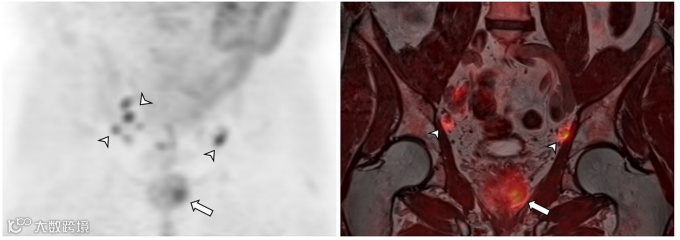

图1. 一名74岁前列腺癌男性的前列腺区域同步11C-胆碱PET/MRI图像。

(a) PET、(b) T2WI、(c) DWI、b值1000、(d) ADC、(e) DCE、(f) Ktrans、(g) Kep 和(h) DCE 得出的iAUC图显示肿瘤侵袭左侧肛提肌(小箭)和左侧原发肿瘤大面积前列腺外扩散(箭头)以及骶骨骨转移(大箭)。PET/MRI上还显示肝转移(未显示),临床分期为T4N0M1c。